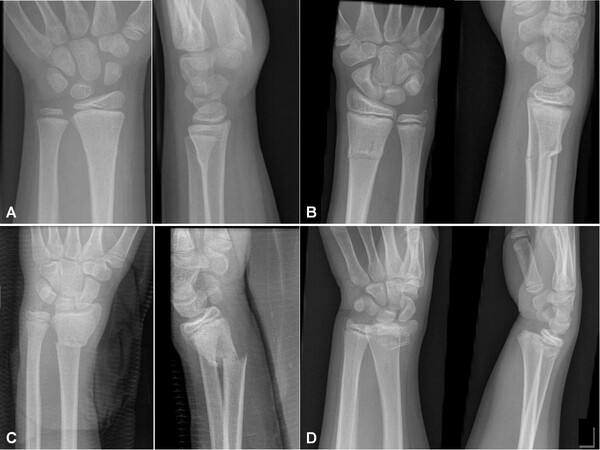

Перелом может быть закрытым или открытым, без смещения или со смещением, простым или оскольчатым. Если линия перелома затрагивает сустав, врач говорит о внутрисуставном переломе. Если сустав не затронут — о внесуставном. Если линия перелома проходит через всю кость, то это полный перелом. А если треснула и не сломалась, то неполный перелом. Иногда вместе с лучевой костью повреждается локтевая кость или связки.

дистальный перелом — перелом нижнего отдела, рядом с запястьем;

перелом диафиза — перелом средней части кости;

проксимальный перелом — перелом верхнего отдела лучевой кости, ближе к локтю. К нему относятся повреждения шейки лучевой кости и головки лучевой кости.

Если отломки смещены, врач может выполнить закрытую репозицию: сопоставить кость без разреза и затем зафиксировать руку.

Если перелом нестабильный, внутрисуставной, открытый, оскольчатый или положение кости нельзя удержать гипсом, может быть необходима операция. Для фиксации используют спицы, пластину с винтами или наружный фиксатор. Такая операция нередко нужна при переломе диафиза — средней части кости, особенно если кость повредила кожу. Операция не гарантирует сращения перелома, особенно, если пациент не соблюдает рекомендации врача и не выполняет упражнения.